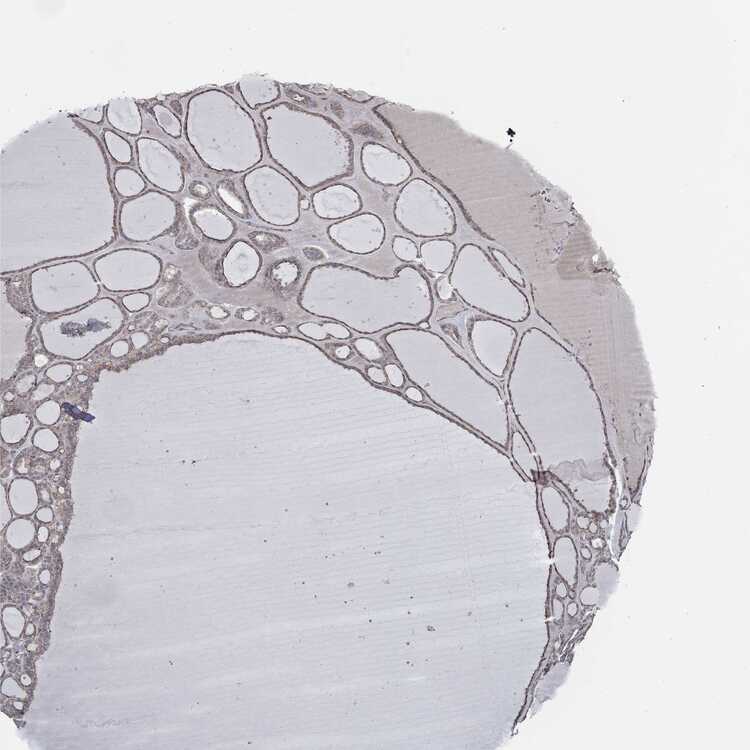

TISSUE PRIMARY DATA THYROID GLAND Show tissue menu

THYROID GLAND - Antibody stainingi

Antibody staining in the annotated cell types in the current human tissue is reported as not detected, low, medium, or high, based on conventional immunohistochemistry profiling in selected tissues. This score is based on the combination of the staining intensity and fraction of stained cells.

Each image is clickable and will lead to virtual microscopy that enables deeper exploration of all samples and also displays staining intensity scores, fraction scores and subcellular localization as well as patient and tissue information for each sample.

Antibody HPA020095Antibody HPA020138Antibody CAB010878Antibody CAB080402

Glandular cells MediumMediumMediumMedium